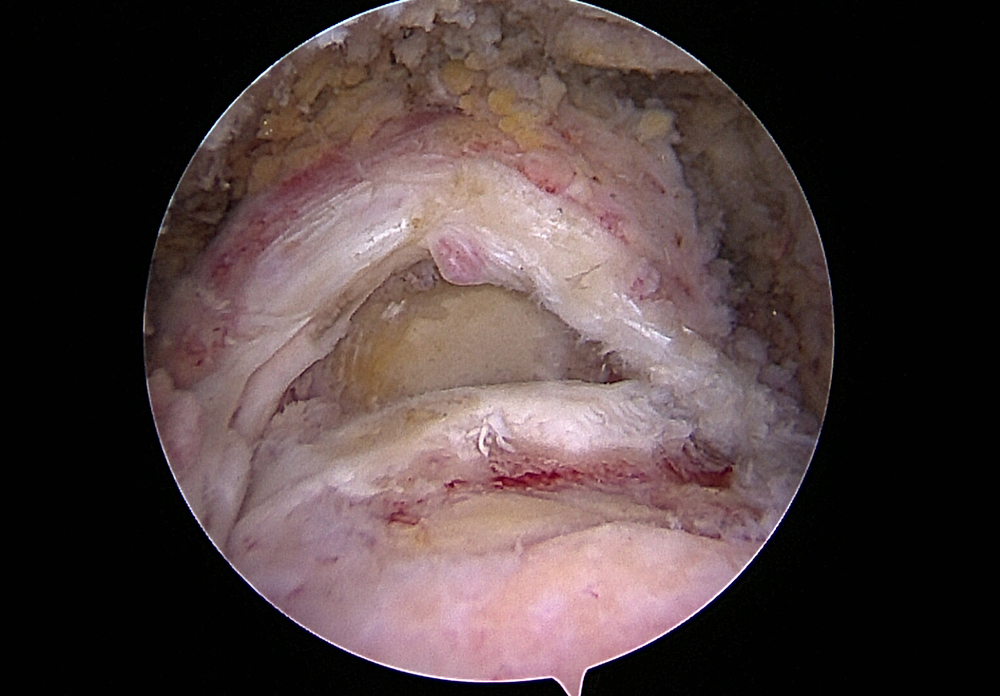

Anchor sutures placed for reconstruction of the rotator cuff

Large rotator cuff tear